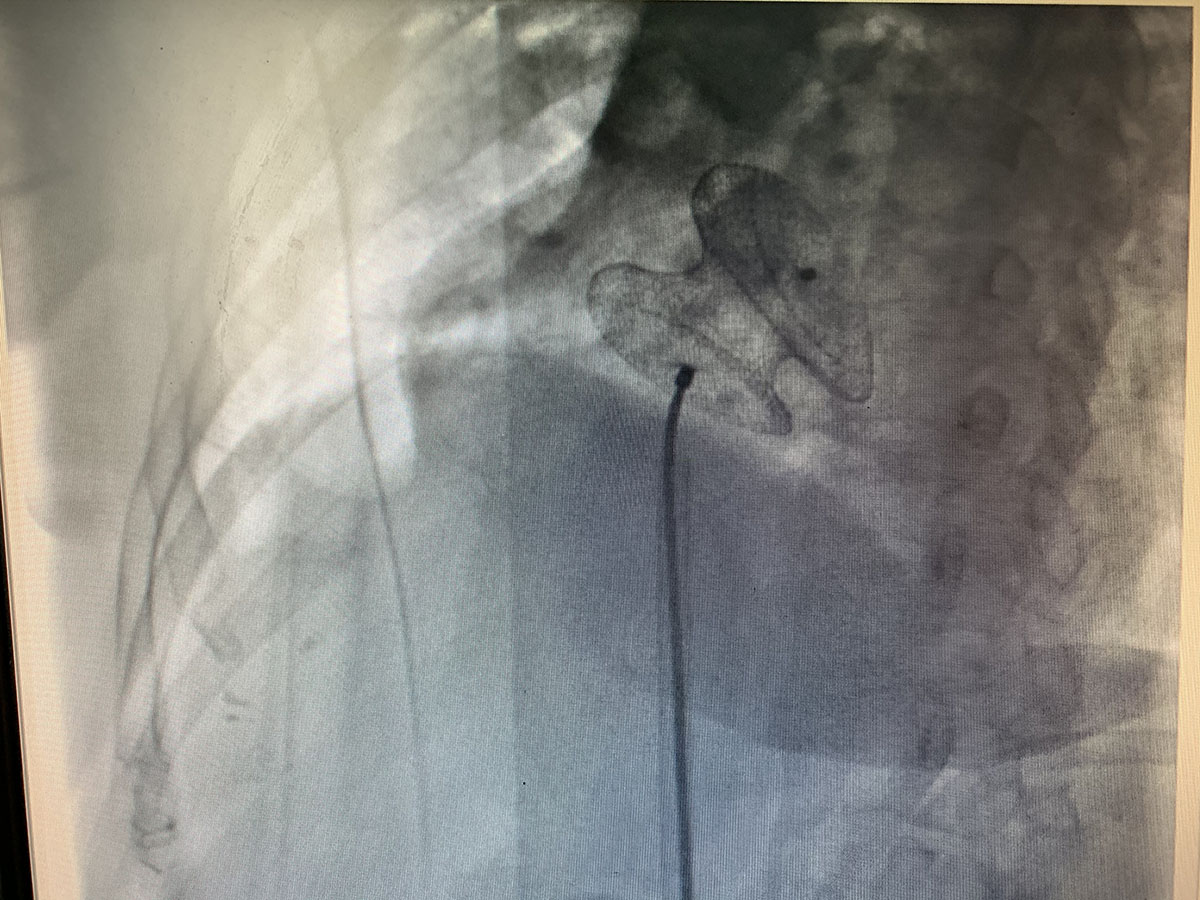

據(jù)了解,王女士,45歲,以發(fā)作性喘息伴胸悶氣短10天,加重1天入住周口市中醫(yī)院心內(nèi)科。患者既往發(fā)現(xiàn)先天性心臟病房間隔缺損10余年,未予重視。入院后經(jīng)行相關生化檢查,心臟彩超,胸片,確診為:房間隔缺損 心力衰竭 心功能III級。于2019年12月14日于我科行房間隔缺損封堵術,手術順利。現(xiàn)已康復出院。